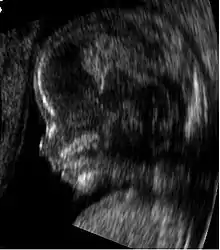

Medical ultrasound is an ultrasound-based diagnostic medical imaging technique used to visualize muscles, tendons, and many internal organs to capture their size, structure and any pathological lesions with real time tomographic images. Ultrasound has been used by radiologists and sonographers to image the human body for at least 50 years and has become a widely used diagnostic tool. The technology is relatively inexpensive and portable, especially when compared with other techniques, such as magnetic resonance imaging (MRI) and computed tomography (CT). Ultrasound is also used to visualize fetuses during routine and emergency prenatal care. Such diagnostic applications used during pregnancy are referred to as obstetric sonography. As currently applied in the medical field, properly performed ultrasound poses no known risks to the patient.[36] Sonography does not use ionizing radiation, and the power levels used for imaging are too low to cause adverse heating or pressure effects in tissue.[37][38] Although the long-term effects due to ultrasound exposure at diagnostic intensity are still unknown,[39] currently most doctors feel that the benefits to patients outweigh the risks.[40] The ALARA (As Low As Reasonably Achievable) principle has been advocated for an ultrasound examination – that is, keeping the scanning time and power settings as low as possible but consistent with diagnostic imaging – and that by that principle nonmedical uses, which by definition are not necessary, are actively discouraged.[41]